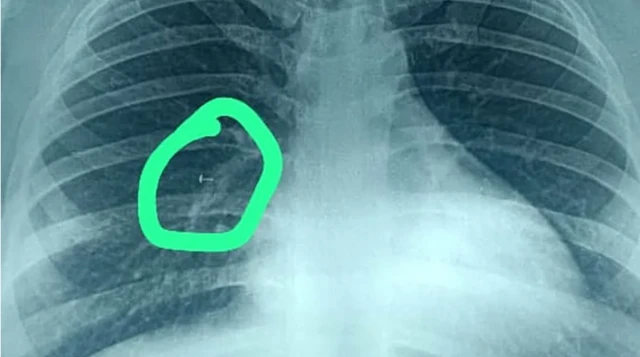

மருந்துகள் பலனளிக்காததால் நுரையீரல் நிபுணரை அவர் அணுகினார். அவரது நுரையீரலில் ஒரு பொருள் இருப்பதை சிடி ஸ்கேன் சுட்டிக்காட்டியது. அதைத் தொடர்ந்து எடுக்கப்பட்ட மார்பு எக்ஸ்ரே அது என்ன என்பதைக் காட்டியது.